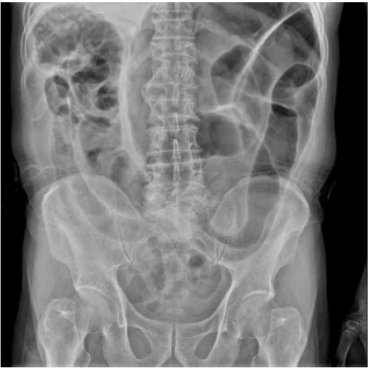

AXR: Coffee-bean sign

급성적인 복부팽만 및 복통을 호소하는 고령의 환자에서 AXR상 "coffee-bean sign"이 확인되므로 구불창자꼬임으로 진단한다.

• 이어 촬영한 AXR상 "coffee-bean sign"이 명확히 관찰되는데, 이는 구불창자꼬임을 시사하는 소견이다. 추가적으로 sigmoidoscopy상 intestinal obstruction 소견 또한 관찰할 수 있다.

• 환자의 임상증상 및 Coffee-bean sign 등의 검사소견을 종합할 때 구불창자꼬임(sigmoid volvulus)으로 진단 가능하다.